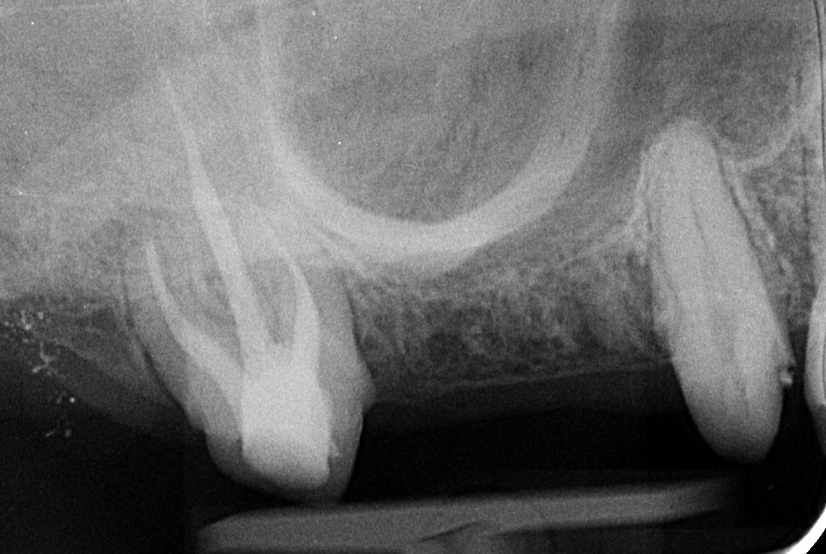

Bár a pótláshoz megoldásképpen akár az implantáció is szóba jöhetett volna, a vizsgálatokból és a röntgenfelvételekből az derült ki, hogy az implantátum behelyezéséhez az alacsonyan elhelyezkedő arcüreg miatt csontpótlásra (sinus-liftre) is szükség lett volna. Ezt megfontolván a páciens inkább a hídpótlás mellett döntött.

hídpótlás rtgfelvétel